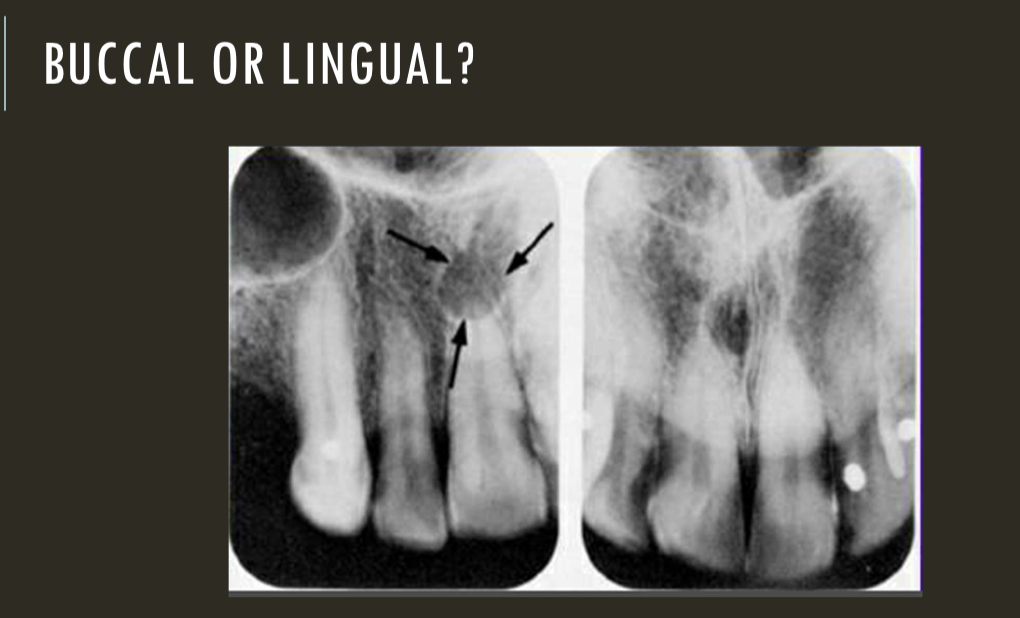

buccal object rule

expose 1st image (PA or bw)

take a second image with a different H or V angulation aka same area different angle

compare images to see how the object shifted in the image

SLOB

lingual

right angle technique

buccal

lingual

lingual

buccal

unable to assess from this single image the objects buccal-lingual position relative to the teeth